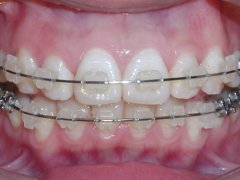

前牙开颌矫正效果好不好?

前牙开颌是一种牙齿畸形,影响外貌美观,影响口腔功能,最终影响人的身体健...【详细】